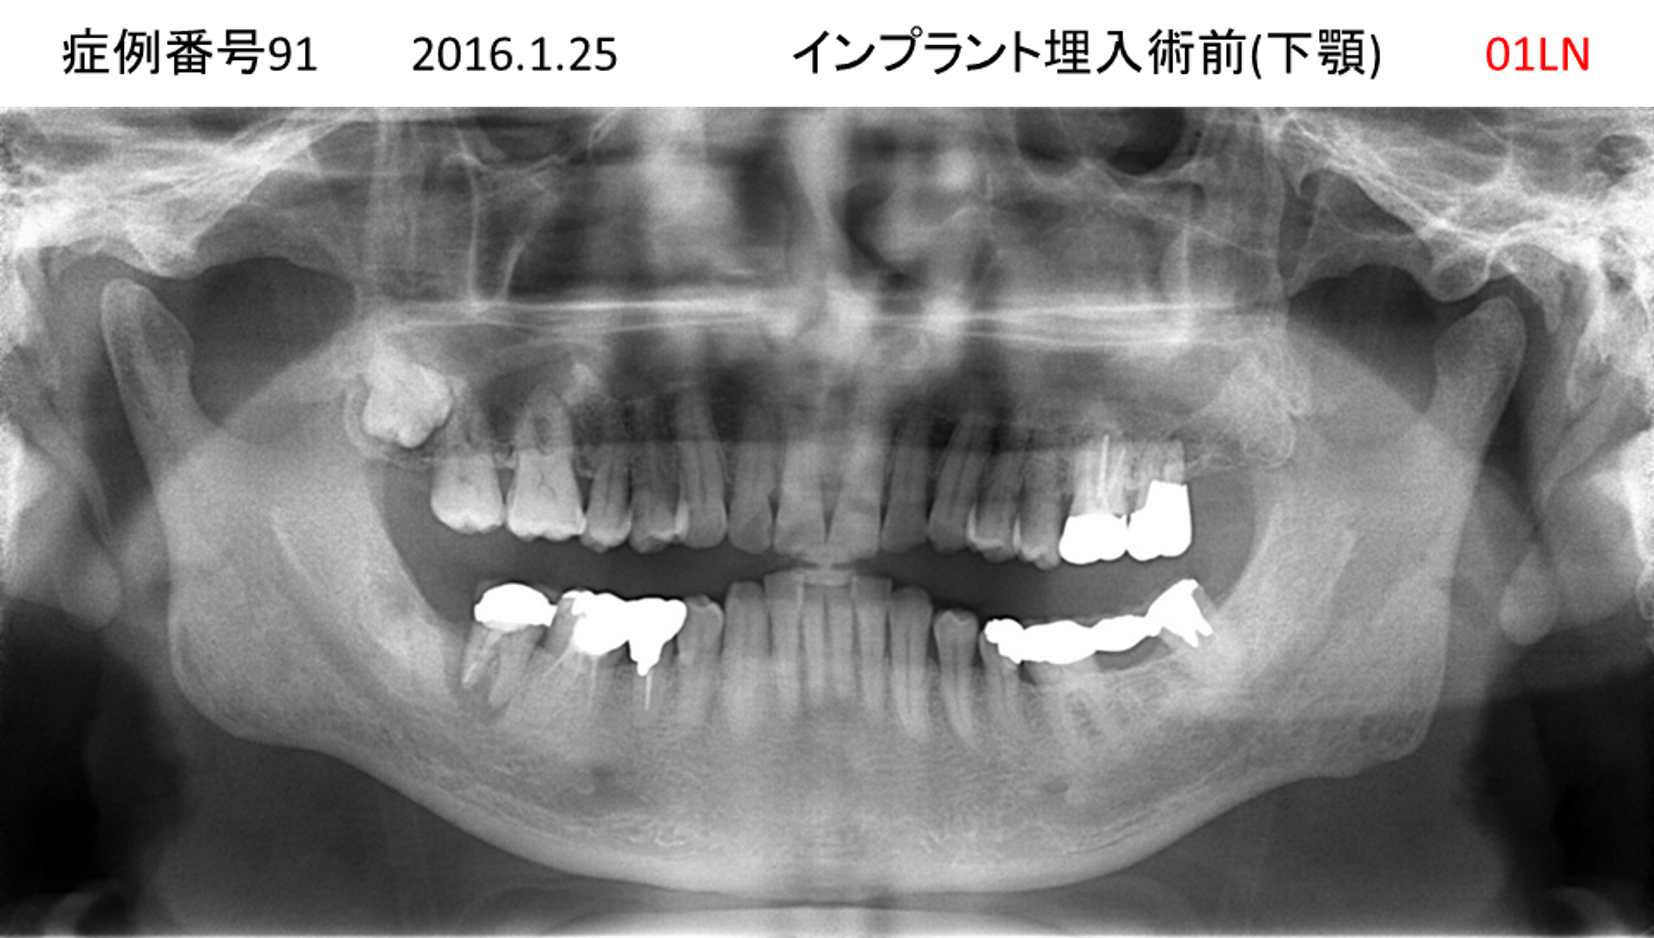

左下の奥歯が痛い患者様のインプラント症例

| 治療名称 |

インプラント |

| 治療費用 |

215万円+税 |

| 治療期間 |

5か月 |

| 患者さんの症状(主訴) |

左下の奥歯が痛い。 |

| 治療内容 |

| 治療結果 |

痛み無く、噛める。 |

| 治療の注意点(リスク/副作用) |

インプラントが壊れたら再治療が必要 |